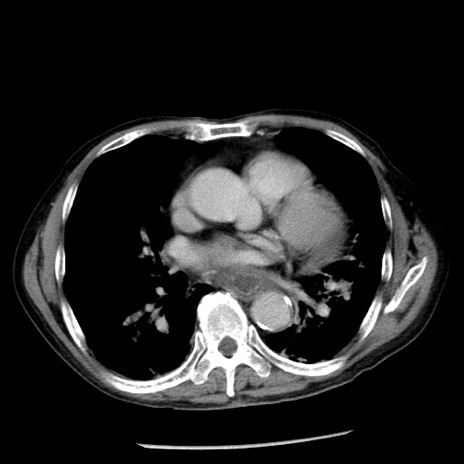

症例26(横断像)

【症例】80歳代男性

【主訴】嘔吐

【現病歴】昨晩2回嘔吐あり、今朝になっても嘔吐あり。来院。

【既往歴】胃潰瘍

【身体所見】意識清明、BT 37.6℃、BP 166/95mmHg、HR 100bpm、SpO2 97%、腹部:平坦・軟、腸蠕動音聴取良好、圧痛なし。

【データ】WBC 21900、CRP 1.46